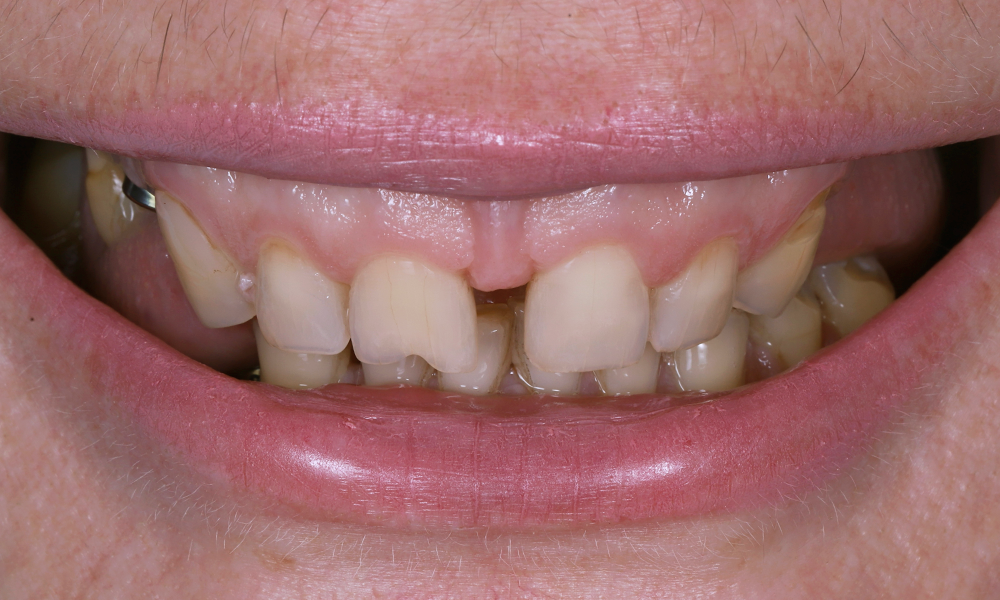

До

Какая ситуация была изначально?

- У пациентки отсутствовали боковые зубы.

- Была выраженная диастема — заметный промежуток между передними резцами.

- Стираемость зубов.

Пациентка хотела не просто «красивые зубы», а гармоничную улыбку, комфорт при жевании и уверенность в себе.